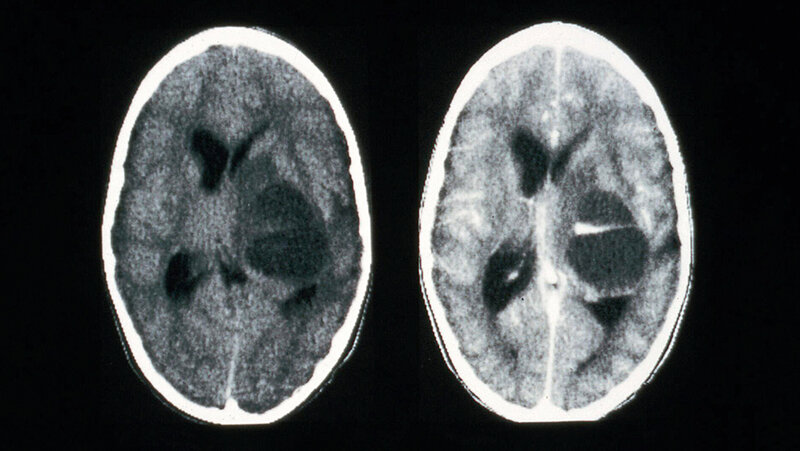

Radiological diagnosis of head injuries with a CT-Scan

Head CT scans are important for detecting brain diseases and diagnosing tumours. The images can help a doctor prepare for surgery. Usually, a head CT is used to provide an initial diagnosis. Another reason can be a check-up on how well a received treatment is working. Reasons that call for a head CT include: strokes, head injuries following accidents, skull fractures, brain tumours, cerebral haemorrhages, cerebral infarcts, vascular malformations, aneurysms or swelling of the brain.